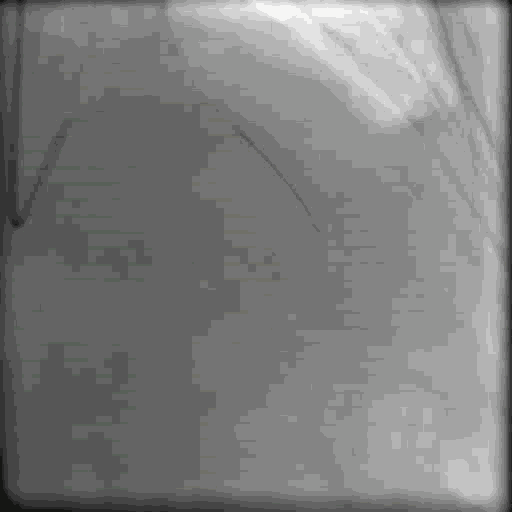

最后结果,LAD CTO成功开通,但远端血流受限,也许之后会慢慢恢复

李妍教授点评:

• 我们应当尽可能开通或挽救所有大的分支。造影显示对角支也存在微通道,开通LAD后应在扩张前尝试放入保护导丝,尽可能保护对角支。CTO开通后丢失了这条重要的分支,十分可惜。

• 我们应当关注CTO开通后的远端血管床。本例中CTO开通后,远端出口过小,血流量不够,会引发支架血栓及支架内逐渐闭塞。应当用IVUS识别是否存在负性重塑或远端痉挛及血肿的问题。